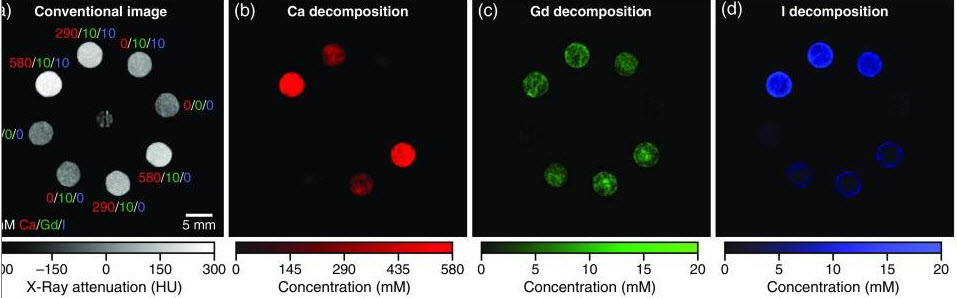

Exciting news! I received the NOA for my NIH application. PCD CT is coming to MD Anderson Cancer Center and Texas Medical Center! Many opportunities like new imaging contrast agents shown from Ryan Roeder (JMI 2019). Thank you NIH and MARS Bioimaging. #radiology #medphys #innovation